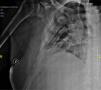

He presented multiple fractures in the ribs and right scapula due to an accidental fall (Fig. 1) and densitometry with signs of osteopenia in the spine. In view of these findings, treatment with phosphate, calcitriol and analgesics was started.